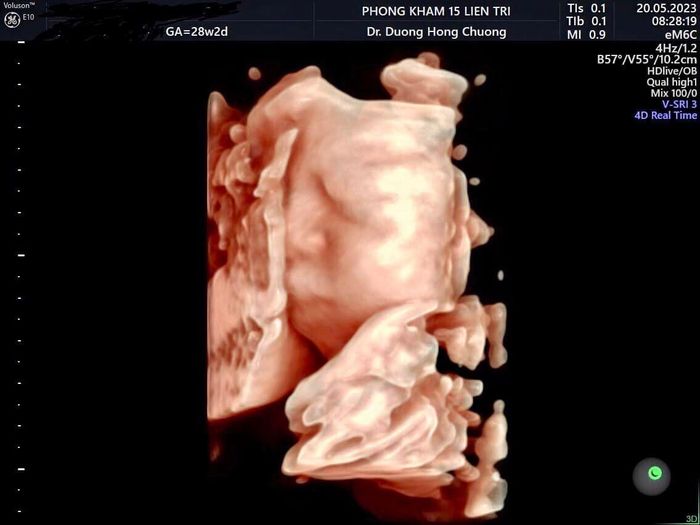

Phòng khám của bác sĩ Dương Hồng Chương được thành lập bởi bác sĩ Dương Hồng Chương, cung cấp các dịch vụ chẩn đoán, tư vấn và điều trị các vấn đề về sản phụ khoa mà các mẹ bầu không nên bỏ qua.

Phòng khám chuyên thực hiện thăm khám, chẩn đoán, siêu âm ổ bụng, chẩn đoán giới tính thai nhi và phát hiện dị tật ở thai nhi. Bác sĩ chỉ thực hiện siêu âm vào những thời điểm quan trọng như 12 tuần, 22 tuần và 32 tuần để chẩn đoán dị tật thai nhi. Hiện tại, bác sĩ Chương công tác tại bệnh viện phụ sản Hà Nội. Phòng khám là cơ sở hoạt động ngoài giờ của bác sĩ Chương nhằm phục vụ tốt nhất cho những bệnh nhân làm việc trong giờ hành chính và không muốn mất thời gian chờ đợi tại bệnh viện.

Với nhiều năm kinh nghiệm và uy tín, Phòng khám của bác sĩ Dương Hồng Chương đã xây dựng được danh tiếng trong việc khám thai cho các mẹ bầu. Định hướng của phòng khám là phát triển thành một hệ thống phòng khám sản phụ khoa uy tín, với đội ngũ nhân sự không ngừng nâng cao trình độ, đầu tư vào cơ sở vật chất để mang lại sức khỏe tốt nhất cho các mẹ bầu.

THÔNG TIN LIÊN HỆ:

Địa chỉ: 15 Liên Trì, Trần Hưng Đạo, Hoàn Kiếm, Hà Nội

Điện thoại: 0948 042 988

Email: [email protected]

Fanpage: https://www.facebook.com/PhongKhamSieuAm15LienTri/